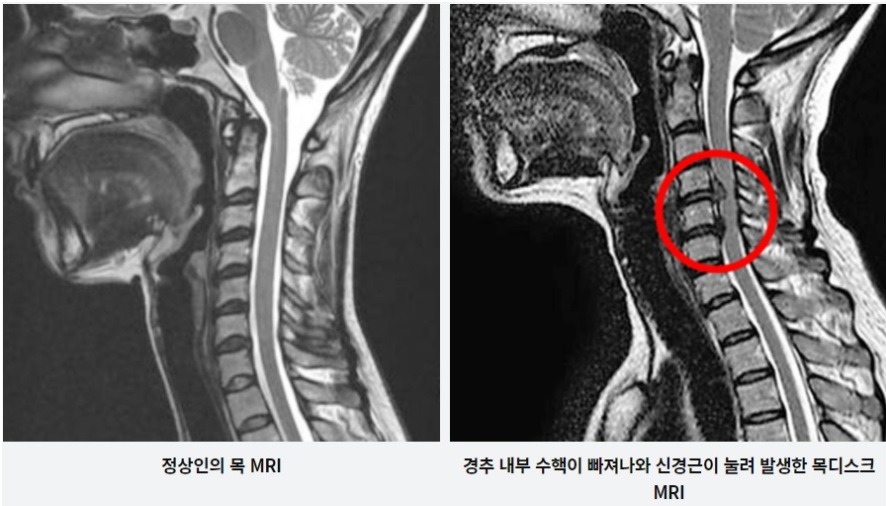

추간판의 수핵이 빠지거나 퇴행성 경추증 및 경추관협착증 등으로 척수가 압박되면 대다수 팔에 힘이 빠지는 것을 느끼게 돼요. 척수가 눌리는 정도이기 때문에 한쪽 팔만 마비될 수 있고요. 하지마는 양팔의 감각이 둔해지고 눈을 감고도 어지럽기 때문에 이러한 목 디스크 증상이 나타나면 무척 위험한 상태가 되기 때문에 빨리 치료가 필요해요.

목디스크 증상 2번째는 다리에 힘이 빠지거나 걷기 곤란한 보행장애가 보여집니다니다. 목디스크 증상은 거의 퇴행성 질환으로 40대부터 조금씩 증상이 생기는 경우가 많이 들어있습니다 이는 그릇된 생활습관이나 오랜시간 앉아있을 때 디스크를 비집고 나온 수핵이 척수를 압박해 신경을 누르게 되어 통증을 느끼게 된다 하였습니다. 증상의 순서의 경우 손에 힘이 빠지고 저리다가, 다리까지 힘이 빠져 걷기 쉽지 않은 보행장애가 생겨나게 된다고 합니다.